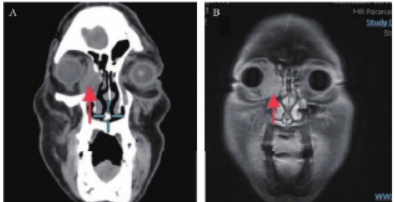

下降,无复视,无眼球活动受限,双鼻腔通畅,鼻腔内结构未见异常,双侧颈部未触及肿大淋巴结。鼻窦增强三维重建CT 提示:右侧眼眶内眦肌锥外可见一约3.5 cm×1.6 cm 大小类圆形肿块影,增强后示轻度强化,眼内肌受压,邻近眶壁骨质欠连续。

鼻窦增强磁共振成像

(magnetic resonance image,MRI)提示:右侧眼眶内侧肌锥外占位性病变,右眼内直肌受压、右侧筛窦外侧壁受累可能性大,右侧眼睑及邻近颌面部软组织肿胀( 图1 )。

图1 影像学资料。A. 患者鼻窦冠状位CT 示右侧眶内占位侵犯内直肌及鼻窦;B. 鼻窦增强MRI 冠状位示右侧眶内占位,右眼内直肌受压,右侧筛窦外侧壁受累。红色箭头示病变部位。